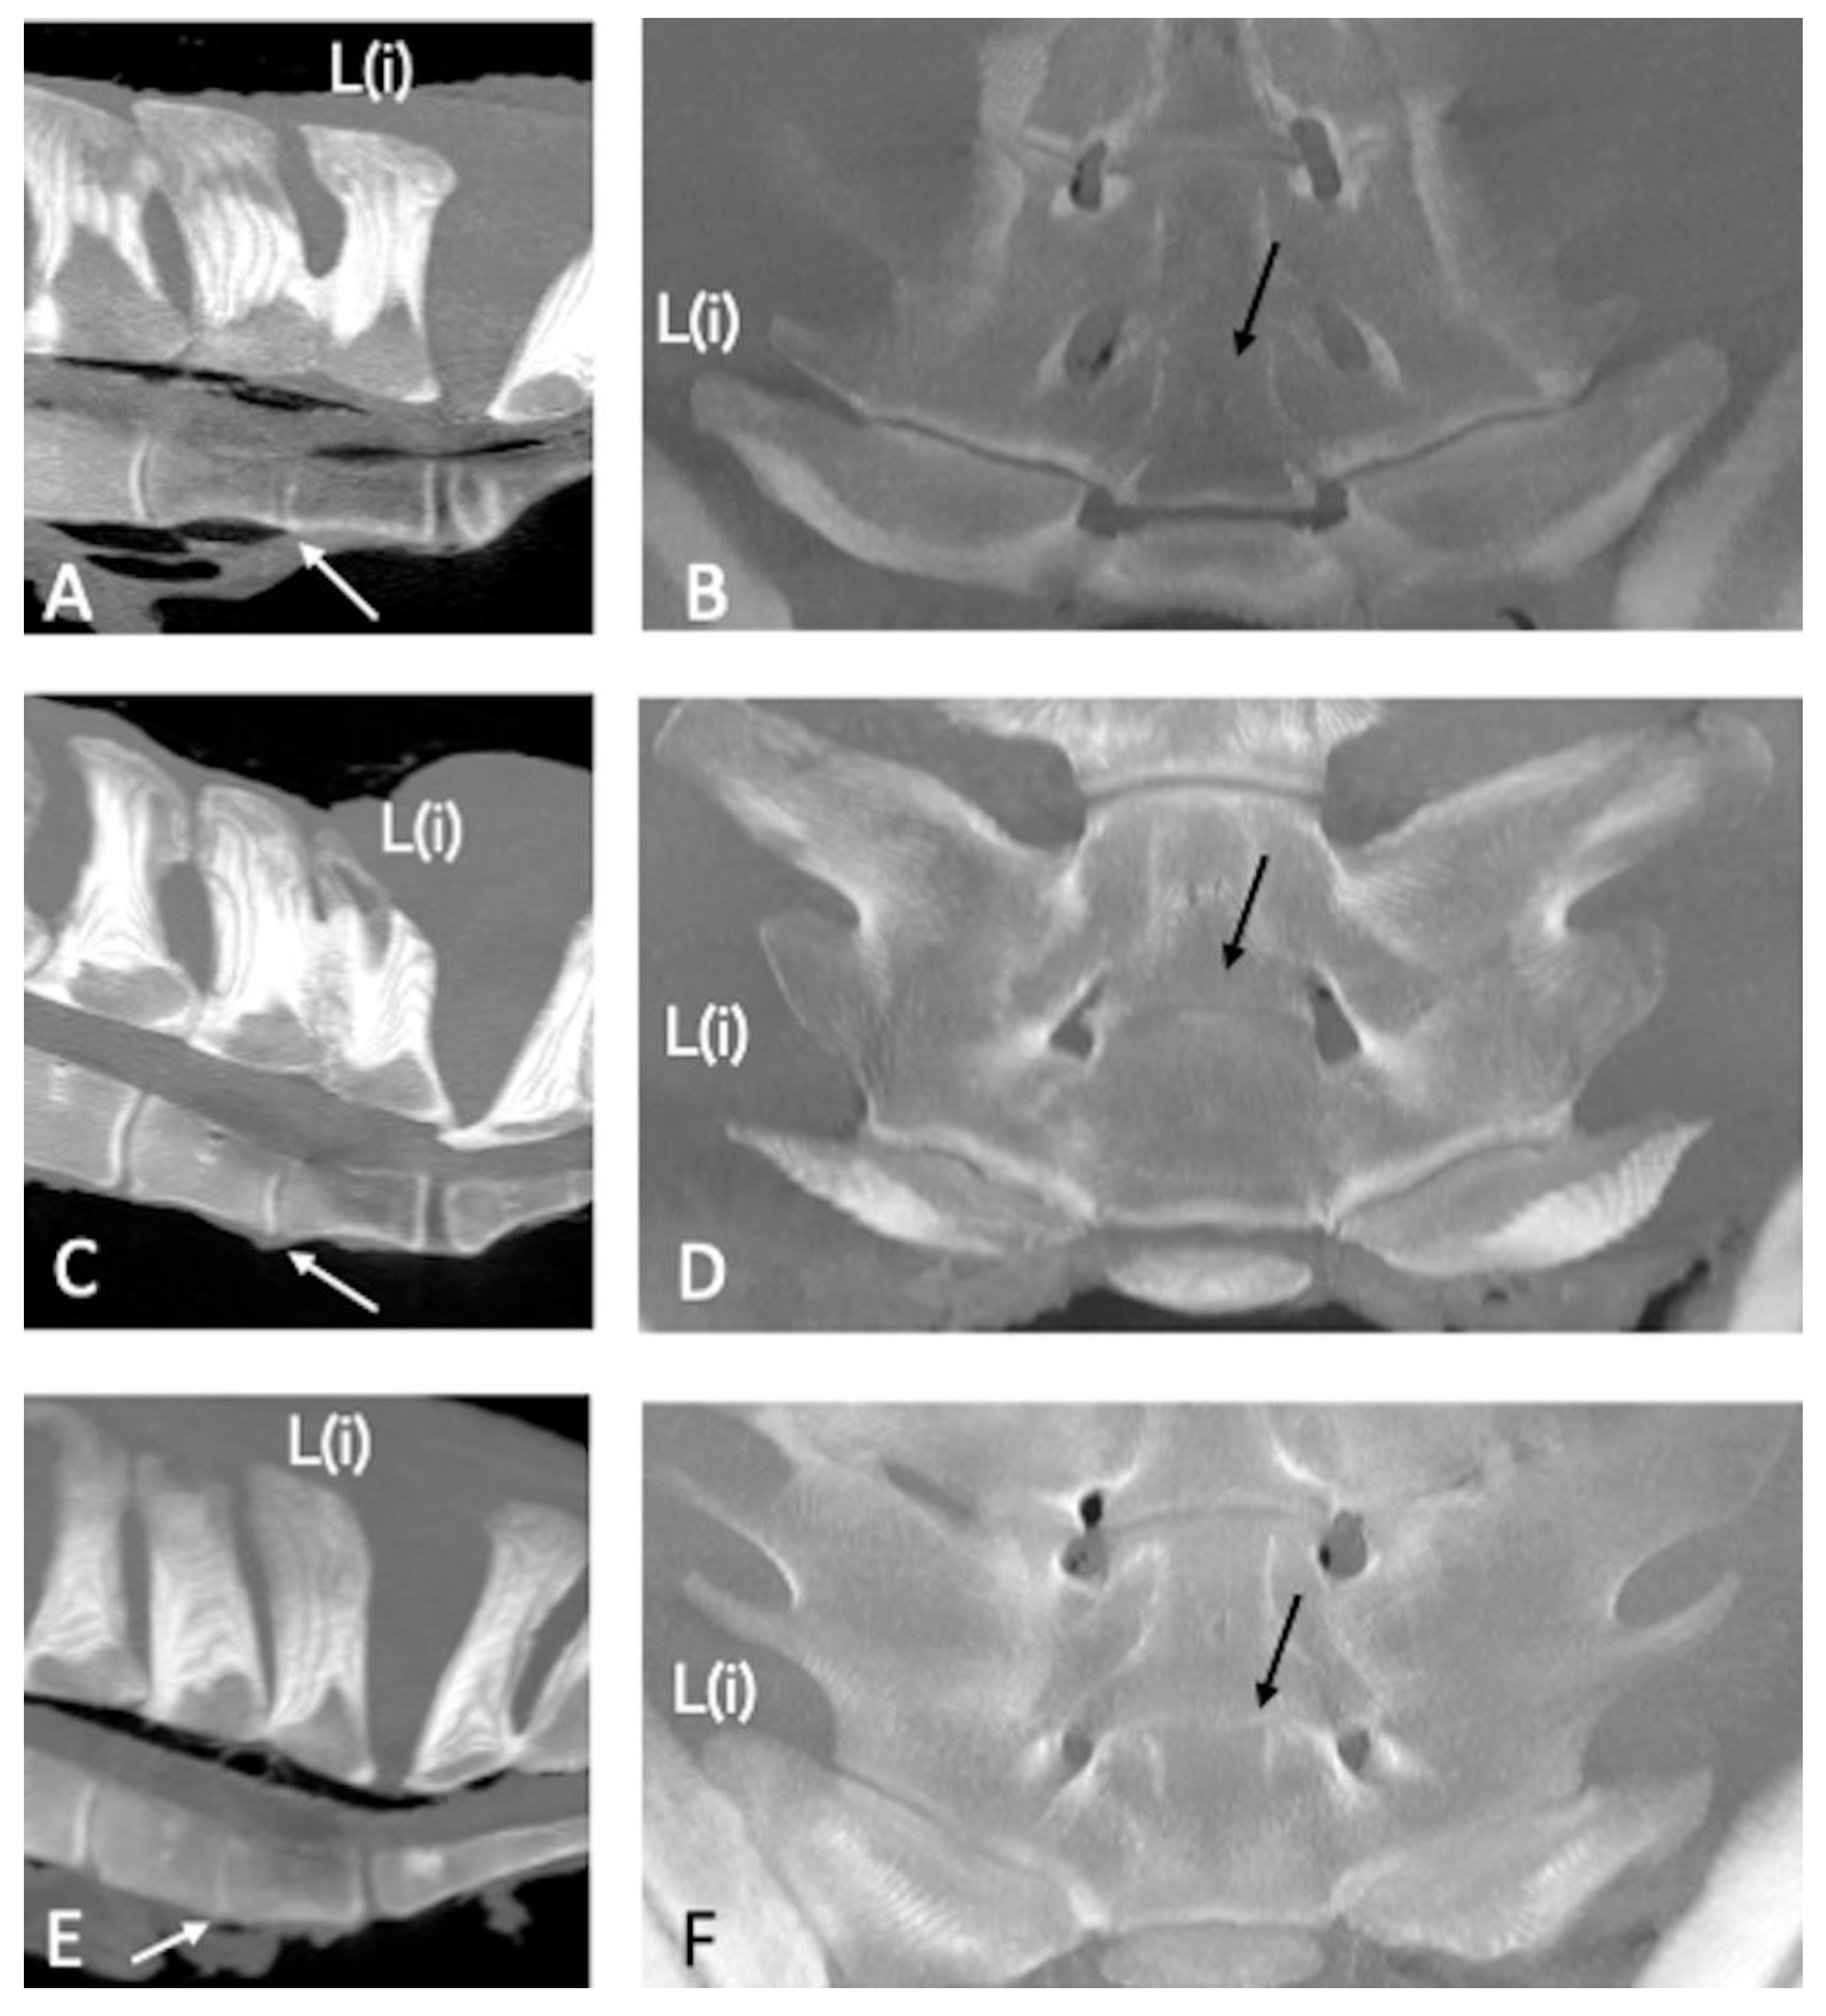

Contact of the SPs was noticed in 21 specimens (54%), and fusion was found in 6 specimens (15%) (Figure 2). The details of location and mean HU are presented in Table 2.

Figure 2. Sagittal (A,C); cranial is toward the left and dorsal (B,D); cranial is toward the top multiplanar reconstruction computed tomographic images of the lumbosacral specimens 8 and 25, using maximum intensity projection (MIP). (A,B) Complete obliteration of the L(iii)-L(ii) interspinous space due to fusion of the dorsal and middle portion of the respective spinous processes (SPs) (asterisk) and severe narrowing of the L(ii)-L(i) interspinous space (arrow). (C,D) Fusion of the middle and ventral portion of the L(ii)-L(i) SPs (asterisk). There is contact on the dorsal and minimally on the middle portion of the L(iii)-L(ii) SPs with reduced density of the bone and lack of compact bone (arrow); the contact is difficult to be seen on sagittal MIP image (C) but clearly highlighted on the dorsal image (D), which show also new bone formation, abaxially. (B,D) Note the absence of increased bone density on the spongious bone surrounding contact or fusion of the SPs. L: left; R: right; L(iv): fourth to the most caudal lumbar vertebra; L(ii): second to the most caudal lumbar vertebra; S1: first sacral vertebra.